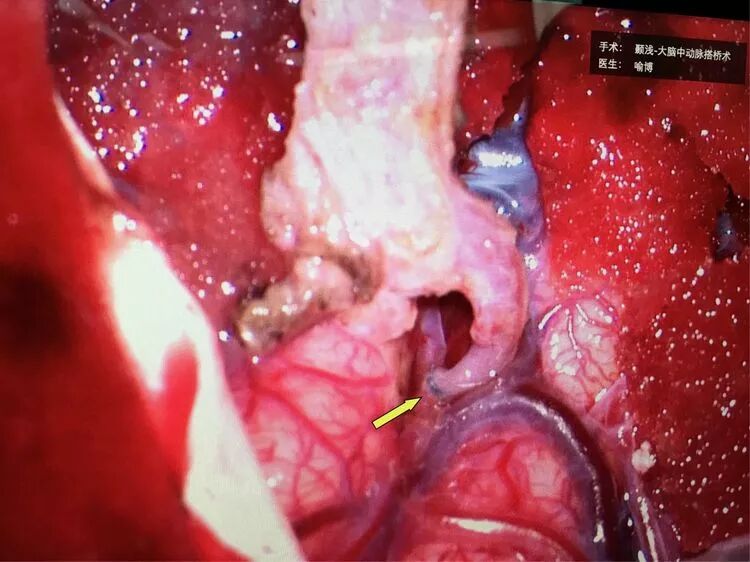

神经外科喻博教授于2018年1月10日为小萍行颞浅动脉-大脑中动脉搭桥术,颞肌贴敷术。此手术为缺血的大脑半球提供直接的代偿供血(搭桥),以及远期的间接代偿供血(颞肌贴敷)。

箭头所示为颞浅动脉额支(供血动脉)与右侧大脑中动脉M4段(受体)经精密的缝合吻合到一起(血管直径只有0.8mm)。